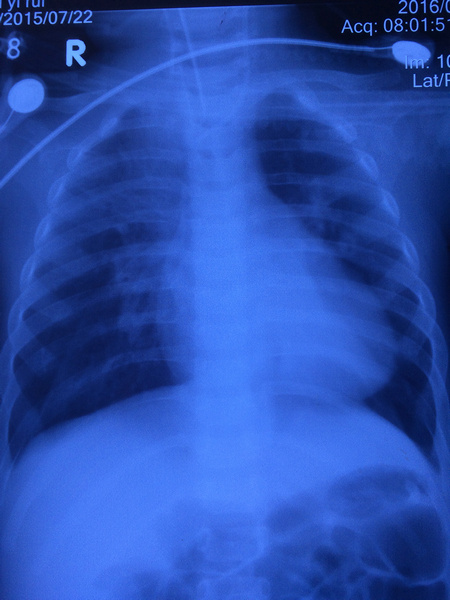

术后心电图

本例患者属于典型肺动脉高压,胸片特征如:右下肺动脉横径增宽,肺动脉段突出,中央肺动脉扩张、外周肺血管丢失形成“残根征”,右房、右室扩大,心胸比增大。

由于心内畸形纠正,术后胸片提示较术前明显好转